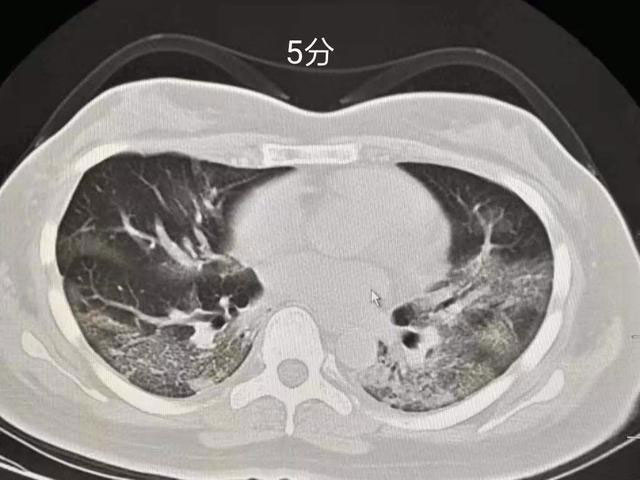

5分:双肺胸膜下区多发斑片状磨玻璃密度影,边界清楚,可短期(几天内)演变为大片实变或者逐渐吸收、纤维化,强烈提示新型冠状病毒感染性肺炎。

临床意义:无论核酸检测是否阳性,依照2019新型冠状病毒(2019-nCoV)感染肺炎治疗,传染病病房隔离。亲密接触者隔离观察。

下图为评分图解